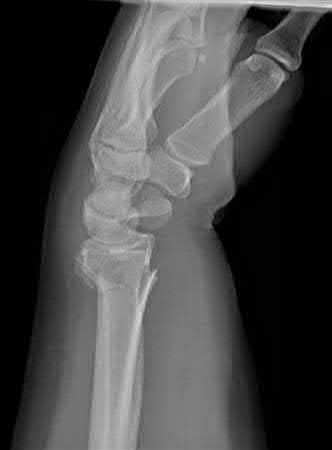

A 38-year-old male suffers the injury shown in Figure A. During operative fixation, free osteoarticular fragments are encountered and reconstruction of these pieces is attempted. Postoperatively, which of the following will have the most beneficial effect on the healing potential of the surviving chondrocytes within these reconstructed articular segments?

Figure A demonstrates a comminuted tibial plateau fracture with significant intra-articular involvement. Basic science evidence has demonstrated that post-operative gentle compressive loading may have a positive impact on articular cartilage healing; however, excessive shear loading may be detrimental.

Irrgang et al provide guidelines for rehabilitation following surgical management of articular cartilage lesions of the knee. They state that after articular cartilage repair, exercises to enhance muscle function must be done in a manner which minimizes shear loading of the joint surfaces in the area of the lesion. The authors also discuss the benefits of gentle compressive loading and motion of the joint, and its positive effects on chondrocyte nutrition.

Furthermore, they recommend a period of protected weight bearing as often being necessary, and that this should be followed by progressive loading of the joint.